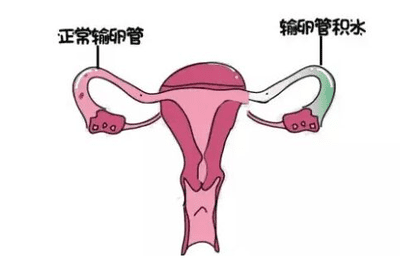

宫外孕是指受精卵在子宫内腔以外着床发育、生长的异常妊娠过程,也称异位妊娠、输卵管妊娠。

什么是宫外孕

正常怀孕受精卵会在子宫内腔着床,但宫外孕顾名思义,是在子宫之外着床。90%以上的宫外孕发生在输卵管,也有少数发生在腹腔、卵巢或宫颈等。

| 宫外孕病因一 | 输卵管炎症

| 宫外孕病因二 | 输卵管手术史或输卵管发育不良